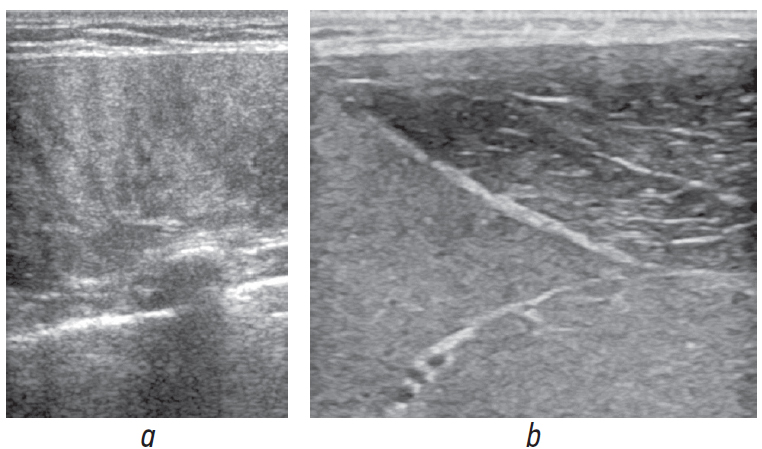

US signs of rhabdomyolysis included a diffuse pronounced increase in echogenicity (homogeneous or heterogeneous), impaired muscle structure cross striation, and large amounts of muscle tissue damage (>30%) (Fig. 1). Rhabdomyolysis was concluded in cases of the detection of all the US symptoms listed.

Fig. 1. Echograms of rhabdomyolysis of skeletal muscles of various anatomical regions: a, back extensor muscle; b, medial and lateral heads of the triceps brachii muscle

Twenty-seven cases met the US criteria for rhabdomyolysis. After laboratory verification of rhabdomyolysis, the diagnostic efficiency of US was indicated by a sensitivity of 68%, specificity of 57, and accuracy of 62%. Despite the low sensitivity of the method in diagnosing rhabdomyolysis, the sensitivity of US in the detection of nonspecific edematous changes in muscle tissue (main group) was 74%.